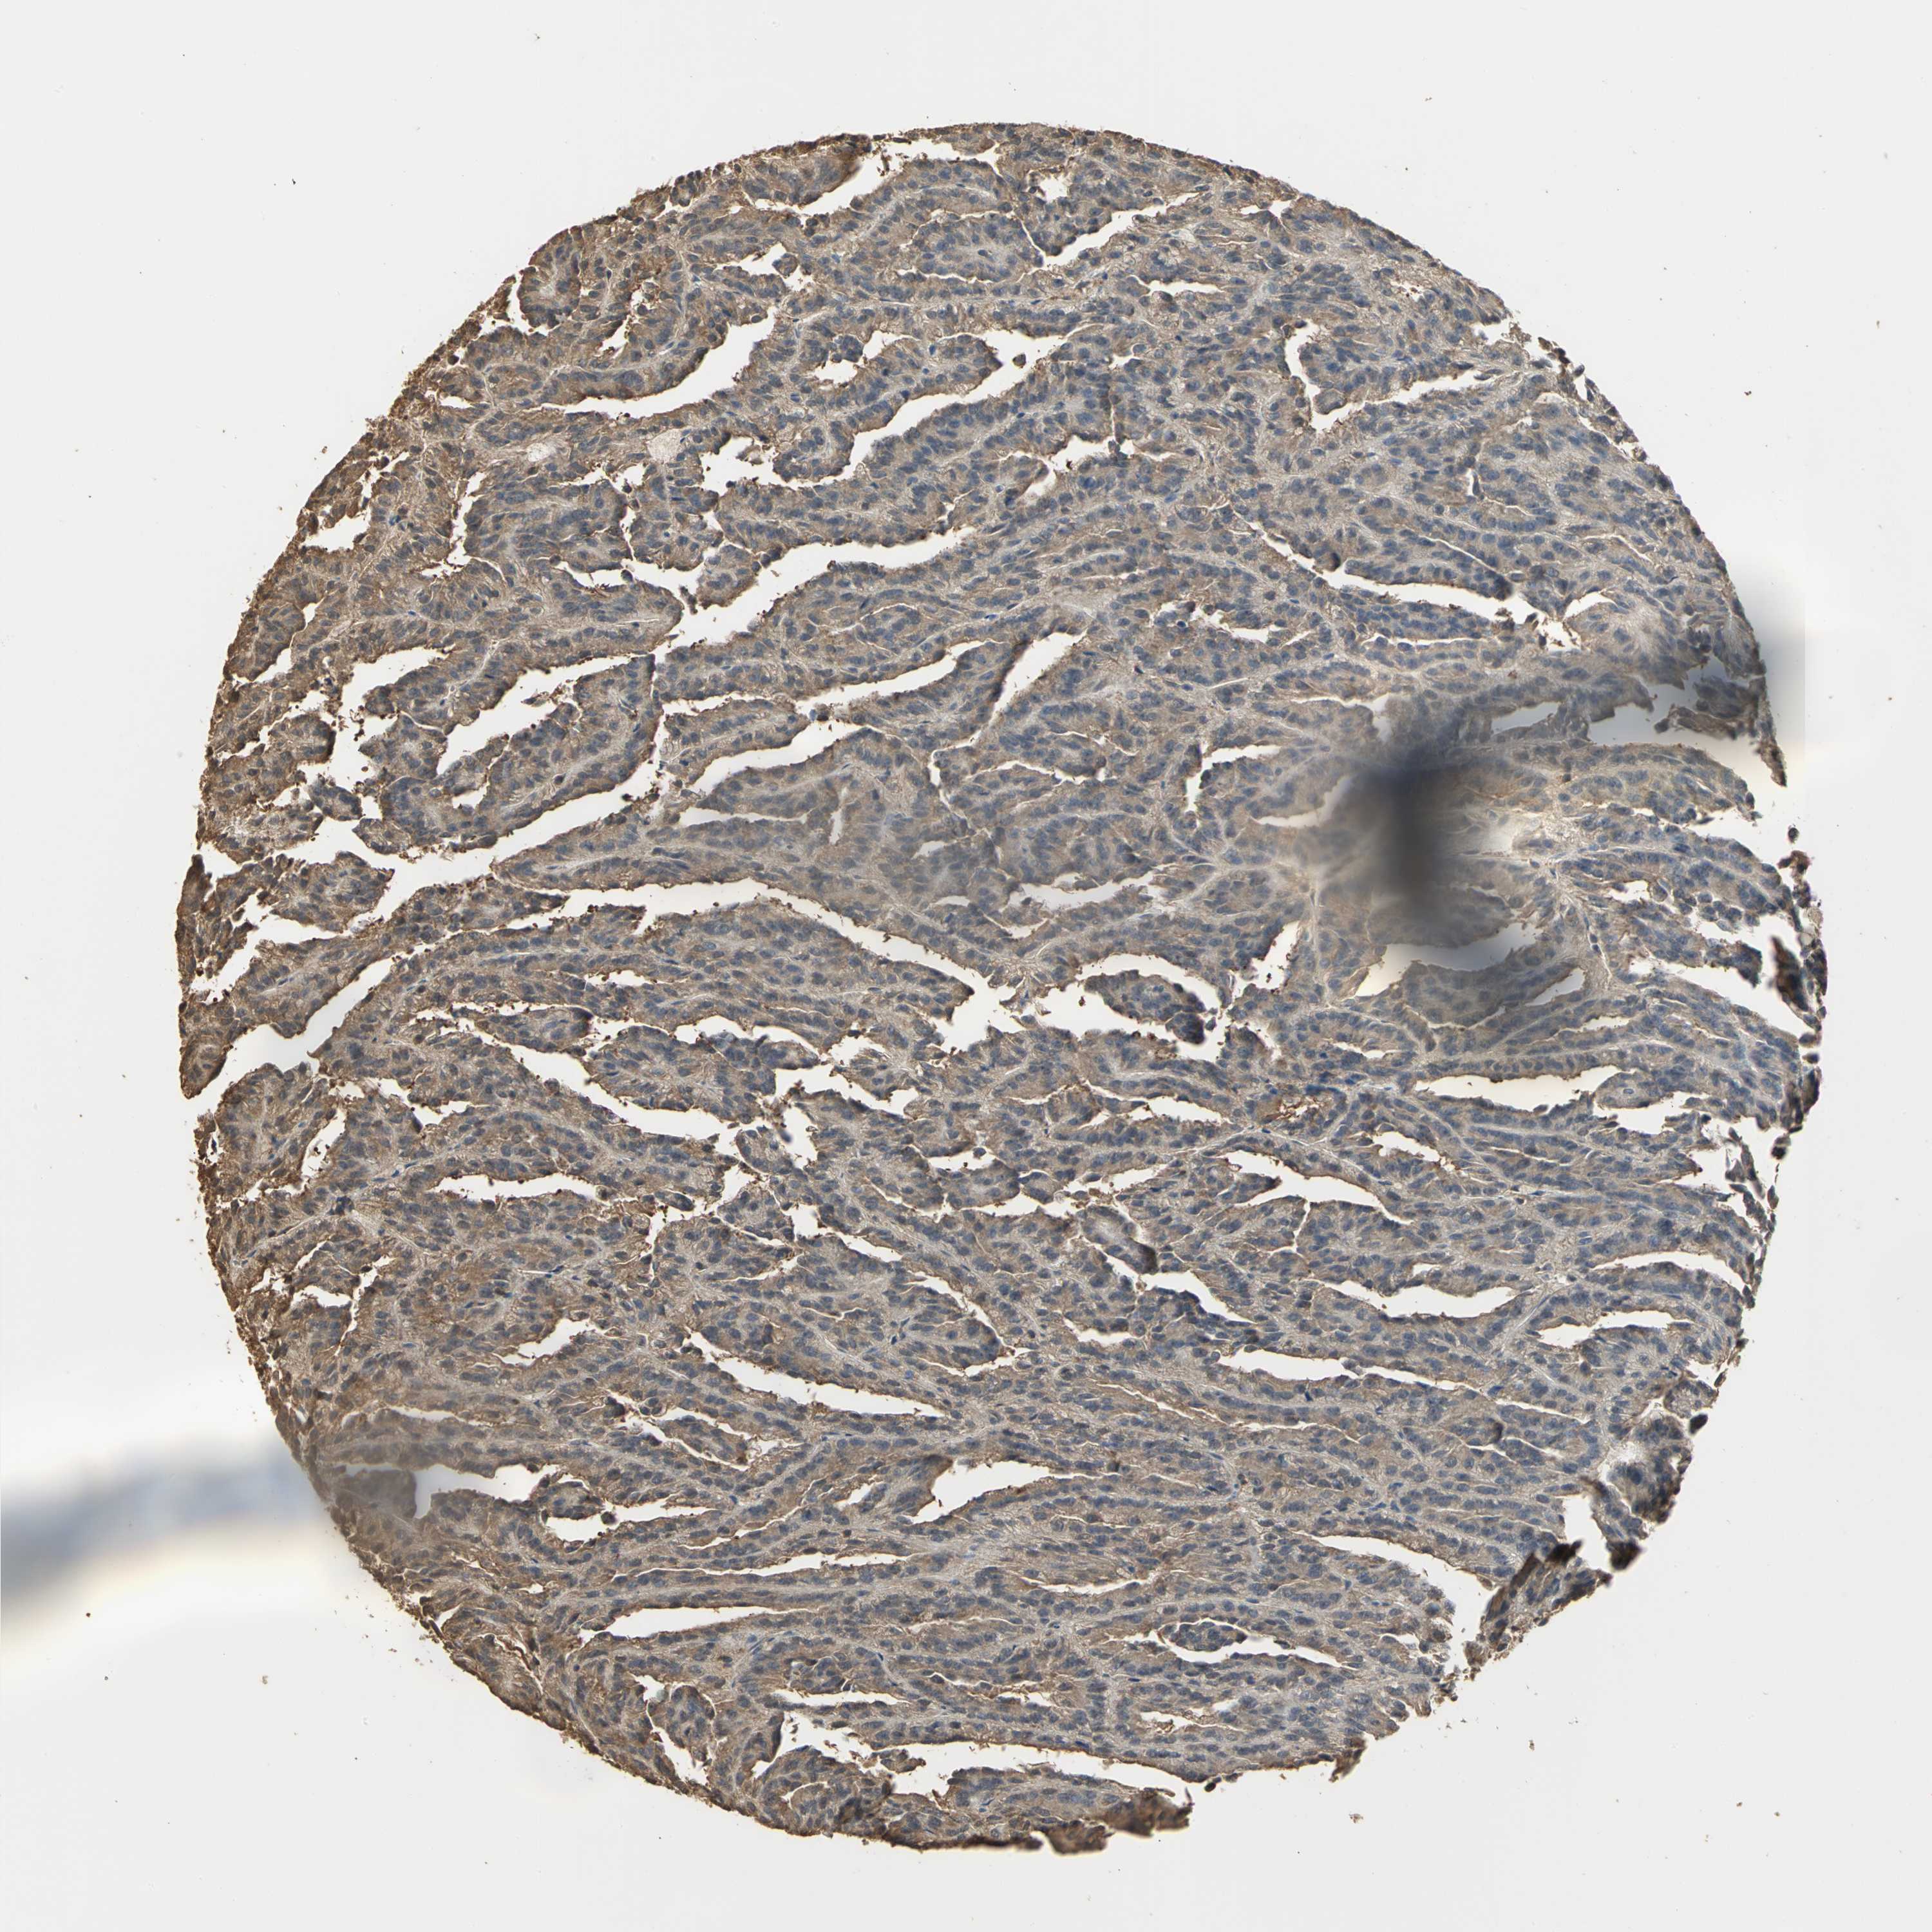

CANCER RENAL CANCER Show tissue menu